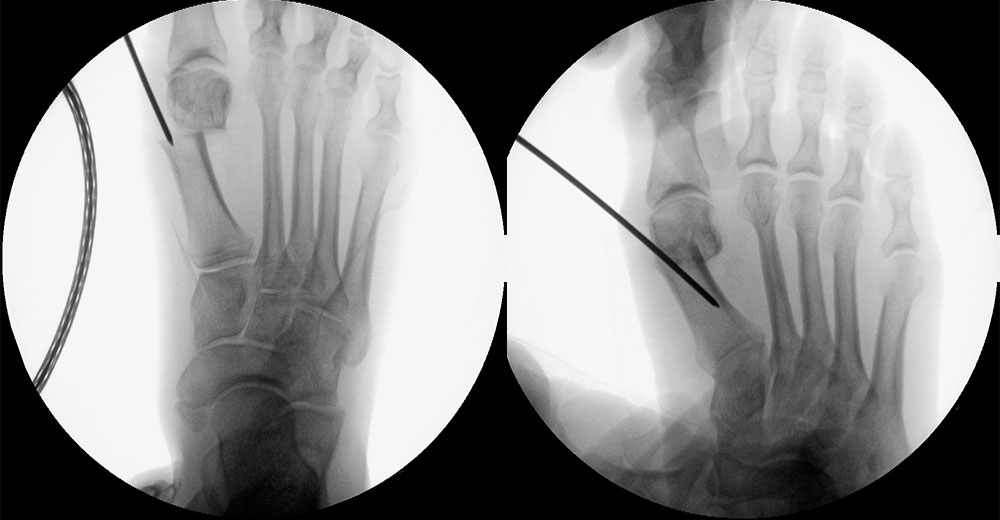

Bei entsprechender Wahl der Osteotomieebene kann auch bei minimalinvasiver Chevron-Osteotomie eine deutliche Plantarisierung des Metatarsalekopfes erreicht werden.

Abbildung 32